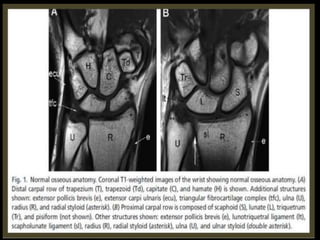

Musculoskeletal Anatomy.